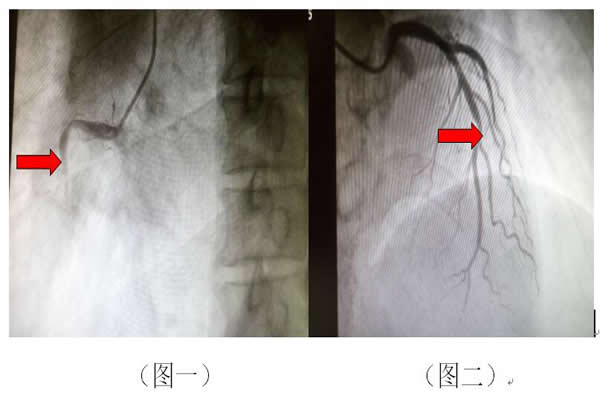

近期,我科收治了一名53歲“急性下壁心肌梗死”的患者,冠狀動(dòng)脈造影檢查提示:“右冠閉塞(圖一)

前降支狹窄70%(圖二)”,急診為患者右冠實(shí)施PCI手術(shù),考慮前降支為臨界病變,暫未予處理。建議患者規(guī)范藥物治療,若效果不佳可考慮介入治療。但出院后患者仍有胸部不適,于6月初再次來我院診治,復(fù)查造影右冠支架良好 ? ? ? ? ? ?